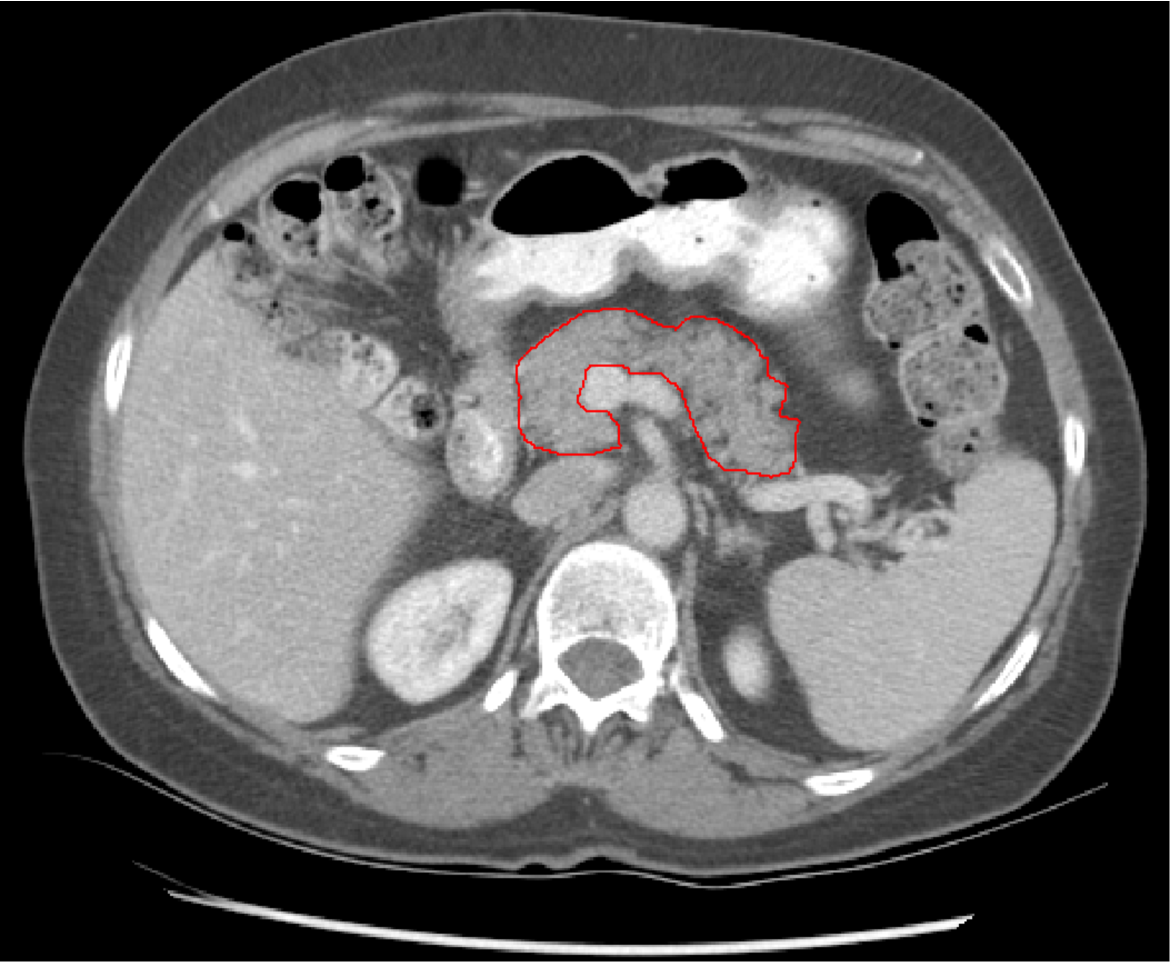

Segmentation of the pancreas is an important input for many computer aided diagnosis (CADx) systems that could provide quantitative analysis, e.g. for diabetic patients. Accurate segmentation could also be necessary for other computer aided detection (CADe) methodologies that aim to detect pancreatic cancer. The literature is rich for the automatic segmentation of numerous organs in CT scans with sensitivities larger 90%, especially for organs such as liver, heart or kidneys. However, high accuracy in the automatic segmentation of the pancreas is a challenging task. The pancreas’ shape, size and location in the abdomen can vary drastically from patient to patient. Visceral fat tissue around the pancreas can cause large variations in contrast along its boundaries in CT. These factors make accurate and robust segmentation of the pancreas challenging. Figure 1 illustrates the noted challenges with a CT slice and ground-truth pancreas segmentation that was established manually by an experienced radiologist (gold standard). We aim to replicate these segmentations using computer vision and medical image computing techniques.

Refer to caption

Figure 1: Axial CT slice of a manual (gold standard) segmentation of the pancreas. The shape and size of the pancreas can vary drastically between patients. Furthermore, densities within the pancreas can vary and the contrast to surrounding tissues can be low in CT.